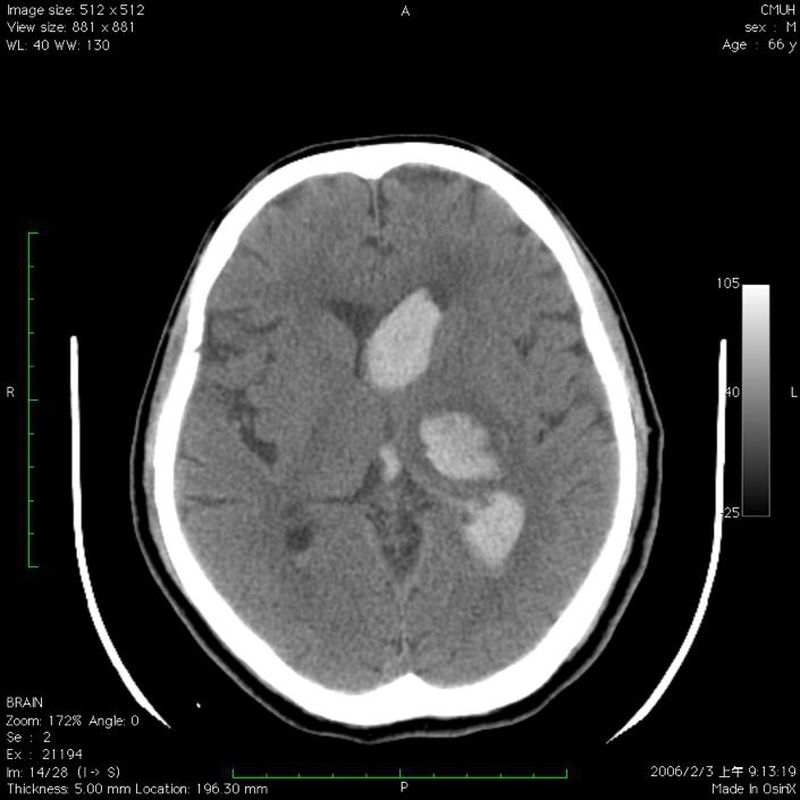

What's your diagnosis?!

1.Epidural hematoma 2.subdural hematoma 3.Intra cranial hemorrhage(ICH)

3 mainly from circle of willis

IVH